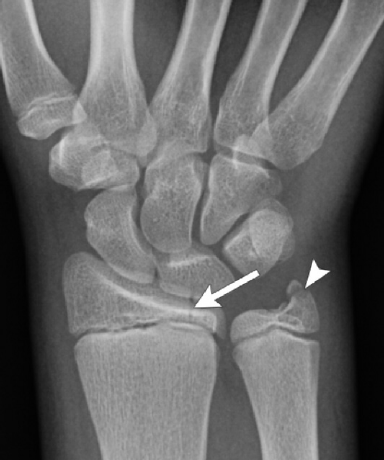

<p>What is wrong with this patient?</p>

What is wrong with this patient?

Nothing, this is a pediatric radiograph. The lines show epiphyseal plates